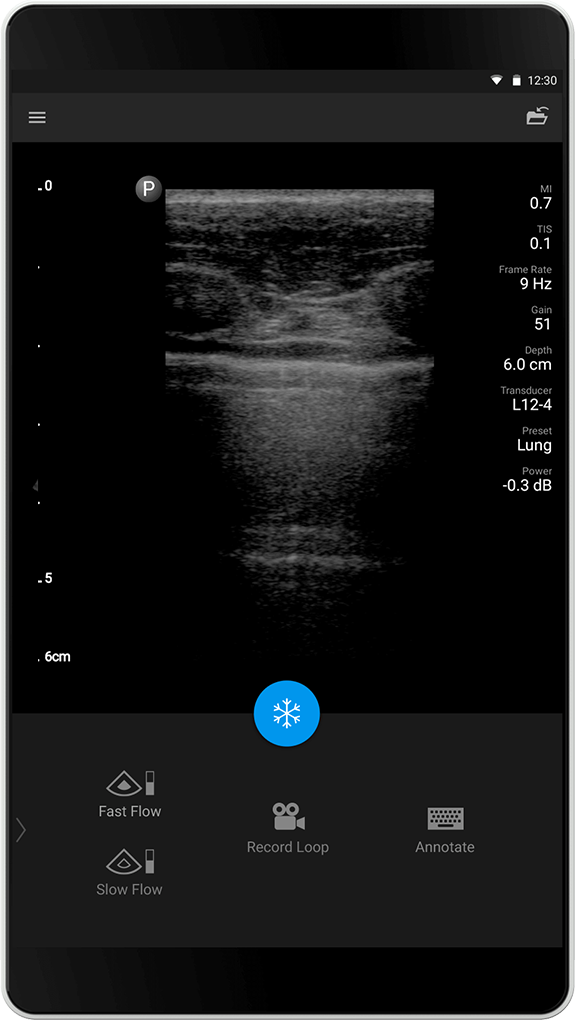

Forhåndsinnstillingen Lung (Lunge) er optimalisert for å fremheve artefaktene som er forbundet med lungeavbildning, og muliggjør enkel visualisering av lungeglidning ved det pleurale grensesnittet. Det vises avanserte avbildingsteknikker (SonoCT, Harmonics og Xres) er ikke aktive/utkoblet i dette presettet/forhåndsinstillingen for bedre fremstilling av tegn som «A-linjer» og «B-linjer».